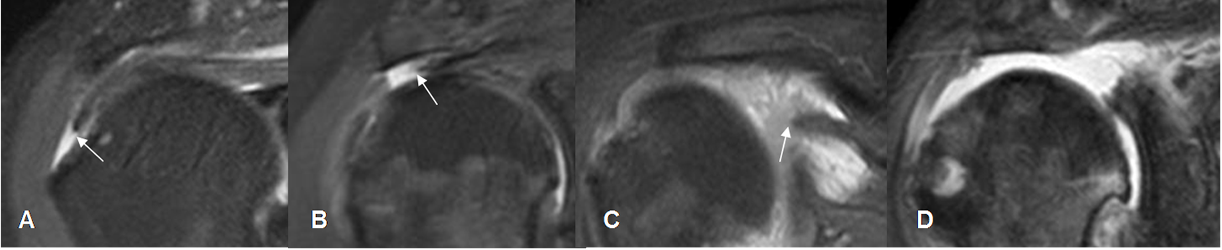

Fig 125. Retracción en las rupturas del supraespinoso.

A, B, C y D: RM coronal en STIR. Diferentes grados de retracción, en rupturas completas del supraespinoso. A: Pequeña, B: Mediana,

C: Larga y D: Masiva.